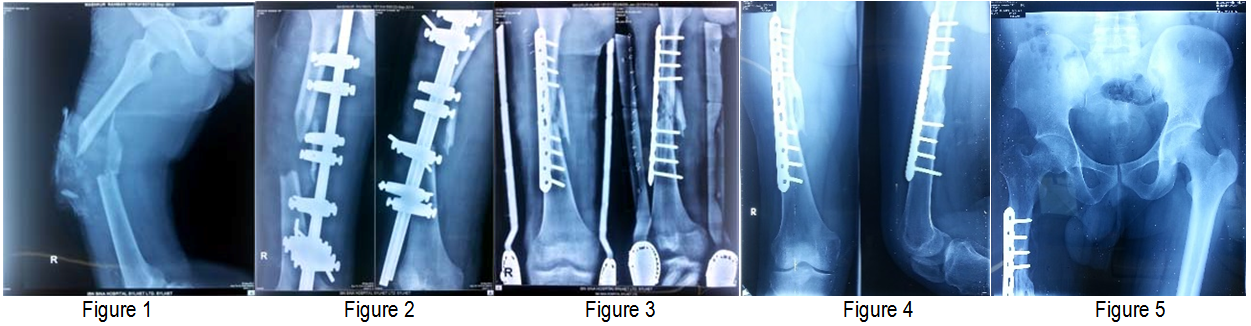

Postoperatively, the patient was started rehabilitation and was discharged after 72 hours of the procedure. Follow up was done clinically and radiologically at 6, 12, 16, 20 and 24 weeks until bony union. The final radiological examinations showed osseointegration of the fibular strut graft (Figure 1–5) with complete healing of the fracture site and bony union was declared at 24 weeks.

Figure 1 Lateral view of thigh (preoperative).

Figure 2 AP and Lateral view of thigh (postoperative).

Figure 3 Open reduction and internal fixation by metaphyseal locking plate.

Figure 4 AP and Lateral view of thigh shows Callus formation after 3 months of operation.

Figure 5 AP view of pelvis including hip joint to proximal thigh.